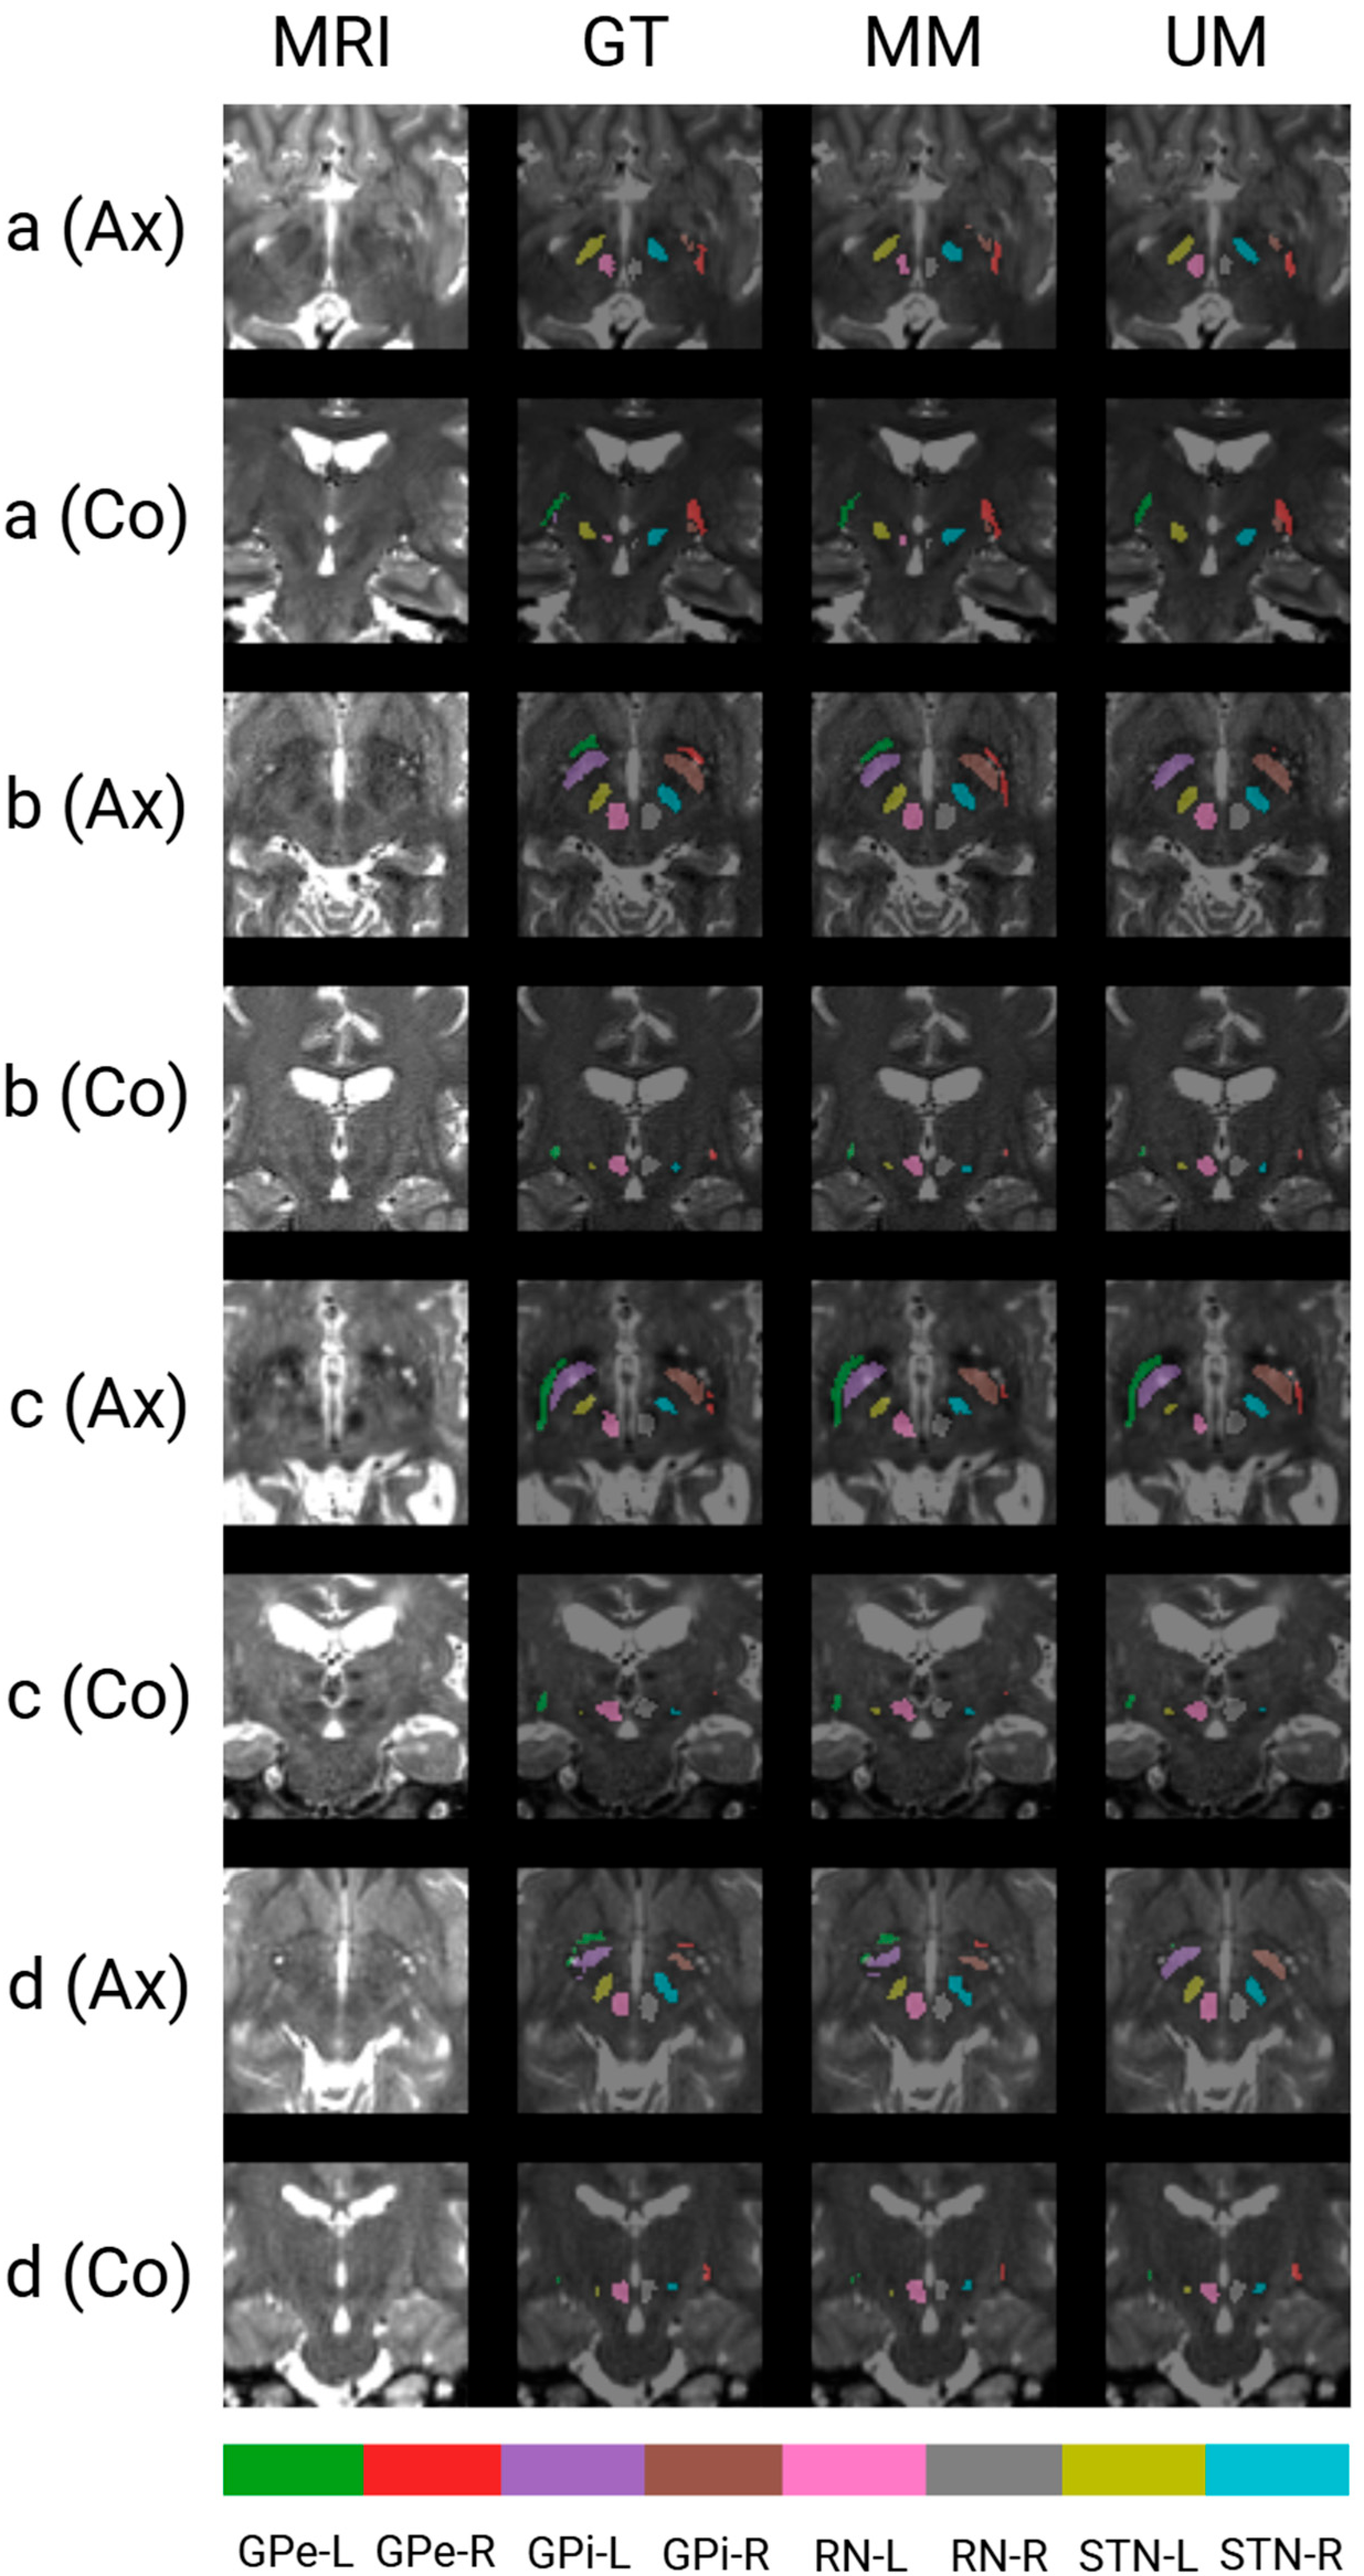

3.3. Qualitative Results